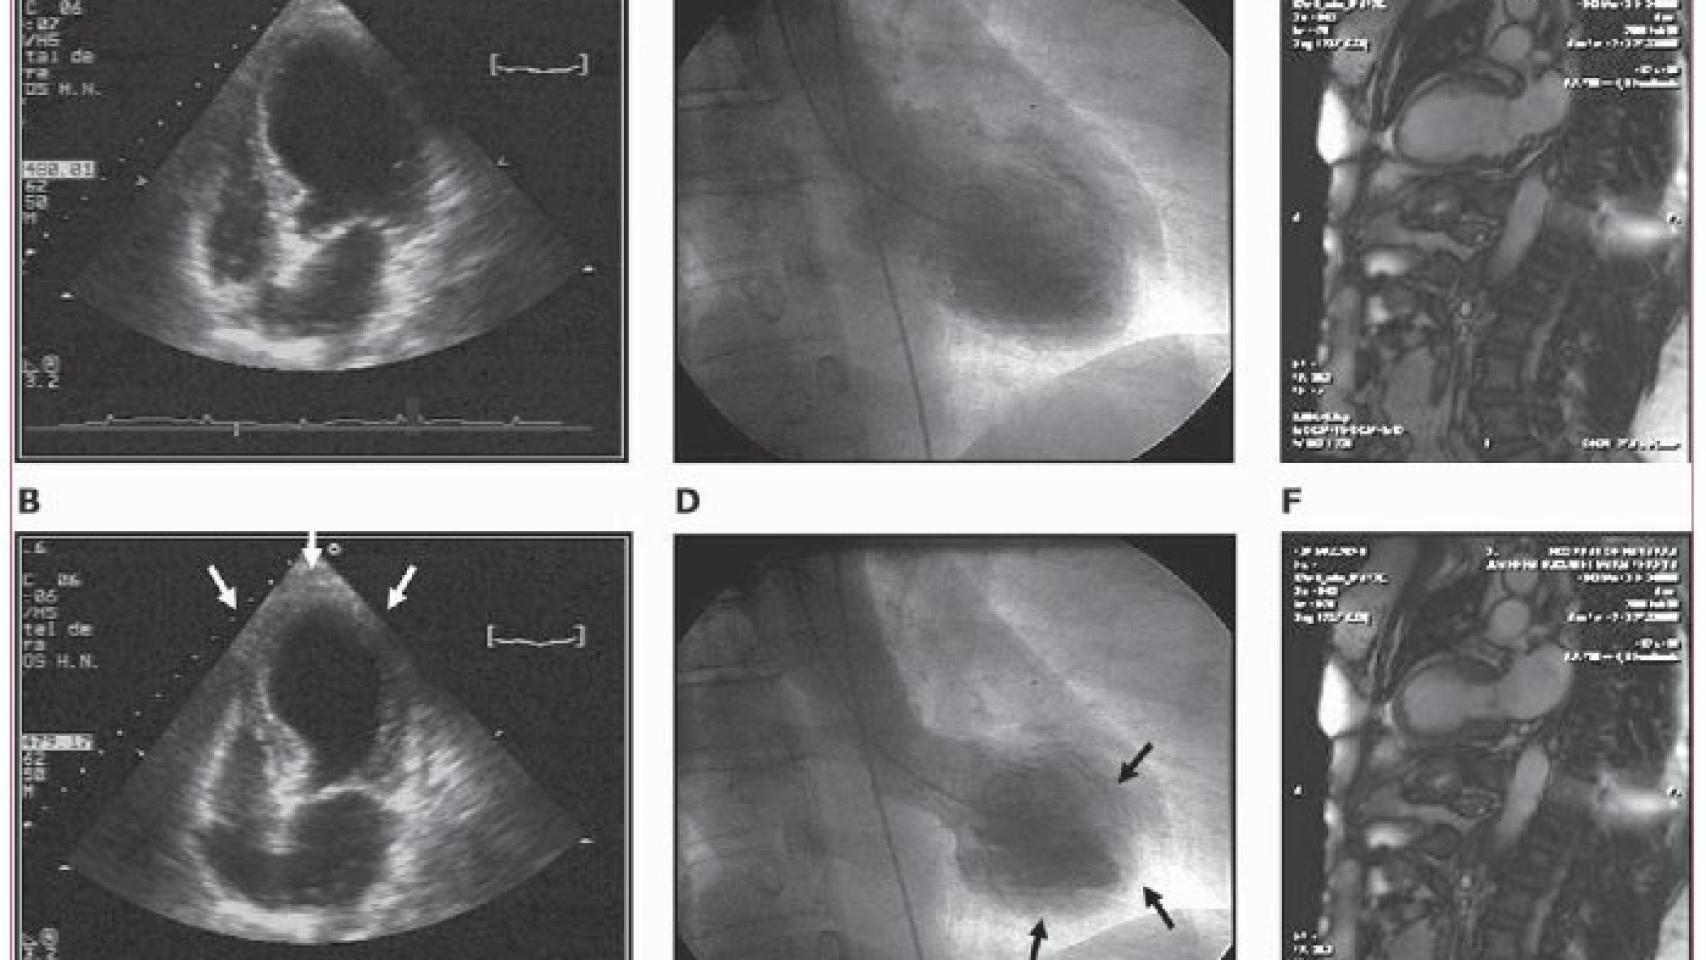

La rotura cardíaca es, literalmente, una fractura o lesión en la pared del músculo cardíaco. Se calcula que, aproximadamente, se producen 135-210 casos de infarto por cada 100.000 habitantes al año en España. Y solo el 1% de ellos acabará sufriendo una rotura cardíaca. Se trata, por tanto, de una complicación muy infrecuente. Pero, a su vez, también muy grave: el 89% de los casos de rotura cardíaca tienen un desenlace fatal.

Los factores que pueden aumentar el riesgo de que se produzca esta rotura son la edad (más de 65 años), el sexo (en mujeres hay más riesgo) o haber sufrido un infarto previo o algún tipo de enfermedad coronaria, entre otros. Nuestro caso solo cumplica el factor de la edad, algo que hace más raro si cabe todo el desenlace.